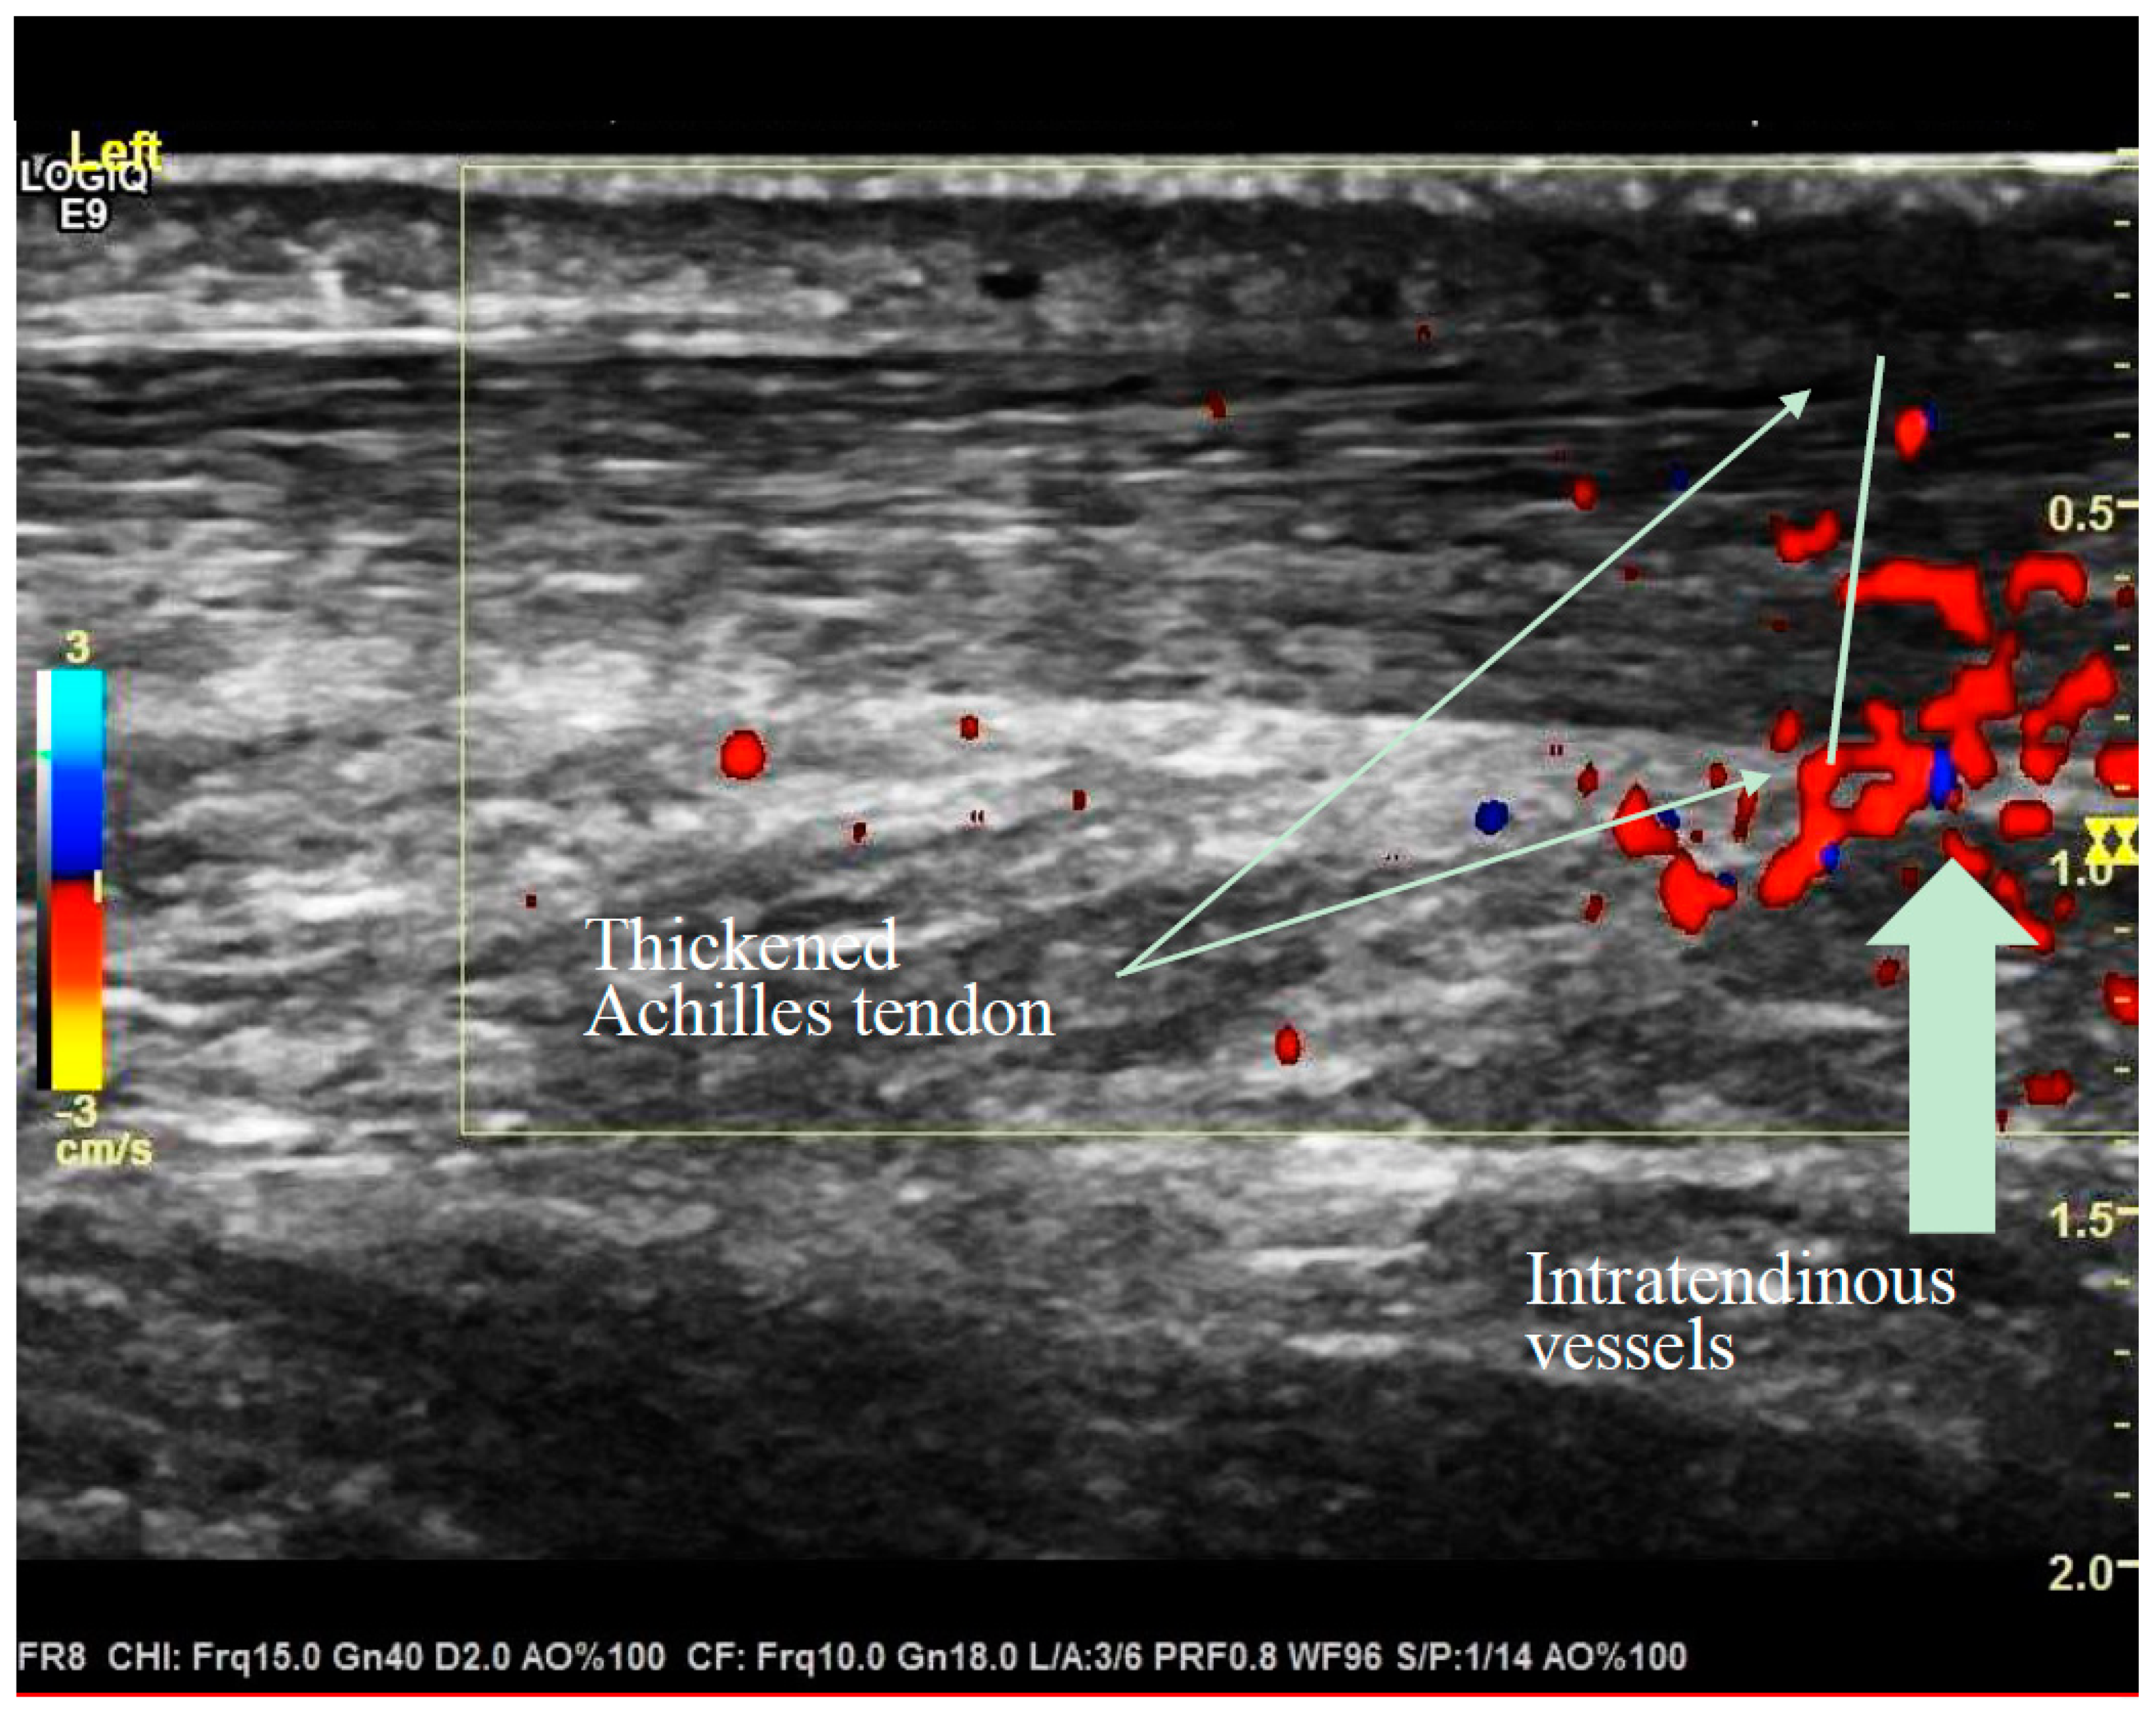

2.4. Ultrasound Criteria

- Maximal thickness in the sagittal plane (mm).

- Structure of the tendon and semi-quantitative evaluation of capillaries according to the modified Öhberg Score [29]).